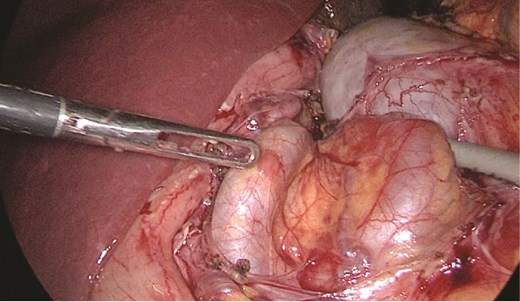

Multidisciplinary discussion was held to evaluate the most appropriate course of action for the patent condition, and the consensus was reached to pursue embolization as a first intervention. Embolization was performed by interventional radiology with no complications post-procedure, and the patient was optimized prior to her procedure. Patient was taken to the operating room in stable conditions. The spleen was enlarged around 20 cm. Inferiorly, the omentum and part of the transverse colon was attached to the spleen (Fig. 3), so we freed the omentum from the splenic tissue. The dissection continued until reaching short gastric vessels and entering the lesser sac (Fig. 4). Once the lesser sac was entered, the splenic vessels were identified (Figs 5 and 6), the splenic vein was hugely dilated with multiple collateral branching vessels at the hilum. Gaining posterior mobilization of the vein was challenging. The splenic artery was tortuous from the insertion around itself (Fig. 7). After complete mobilization of the fundus, we elected to divide each vessel starting with the splenic artery so we can achieve full mobilization of the vein (Fig. 9). After controlling the splenic artery, the splenic vein was dissected proximal to the splenic hilum (Fig. 8). It was hugely dilated and its wall is thickened secondary to AV fistula. It was difficult to achieve circumferential dissection, so we decided at that moment to convert to laparotomy to complete ligating the vein and to retrieve the specimen (Fig. 10a and b).

Splenic vein mobilized from the side. Clips seen on branches of the vein.